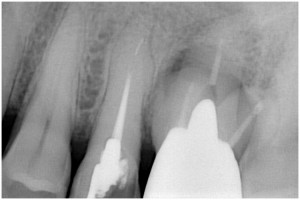

術前

同拡大

抜歯後

抜歯後GBR

GBR後

同拡大像